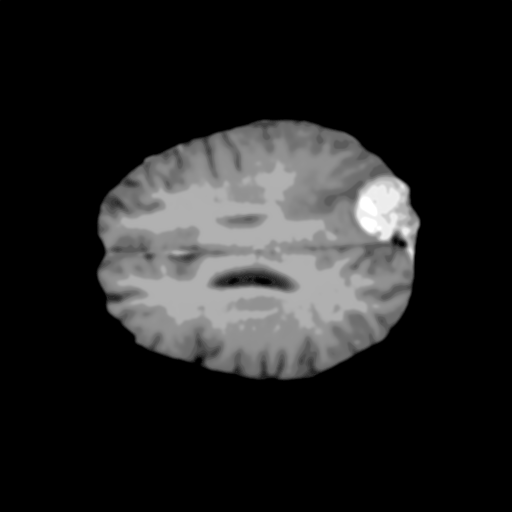

Extensive experiments have been performed in the current setup, and experimental outcomes are reported with the demonstration of numerical and statistical analyses using the proposed QFS-Net, QIS-Net [39], convolutional U-Net [18] and Residual U-Net (URes-Net) architectures [20]. The human expert segmented skull-tripped contrast enhanced DSC brain MR input image slices of size and ROIs are provided in Figure 5 as samples. The demonstration of QFS-Net segmented images followed by the essential post-processed outcome on the slice no. for class level with four distinct activation schemes () are shown in Figure 6. It is evident from the experimental data provided in Table LABEL:tab1 that the proposed QFS-Net performs optimally for the -connected quantum fuzzy pixel information heterogeneity assisted activation () with and gray scale set in comparison with other thresholding schemes and gray scale sets under the four evaluation parameters () [44]. The segmented tumors obtained using the proposed self-supervised procedure under class transition levels with four different thresholding schemes , , and are demonstrated in Figures 7- 8 for the class boundary sets and [39], respectively. The segmented images using the remaining two class boundary sets ( and ) [39] are provided in the supplementary materials section. The segmented ROIs describing the whole tumor region after the masking procedure using QIS-Net, U-Net and URes-Net are also reported in Figure 9.